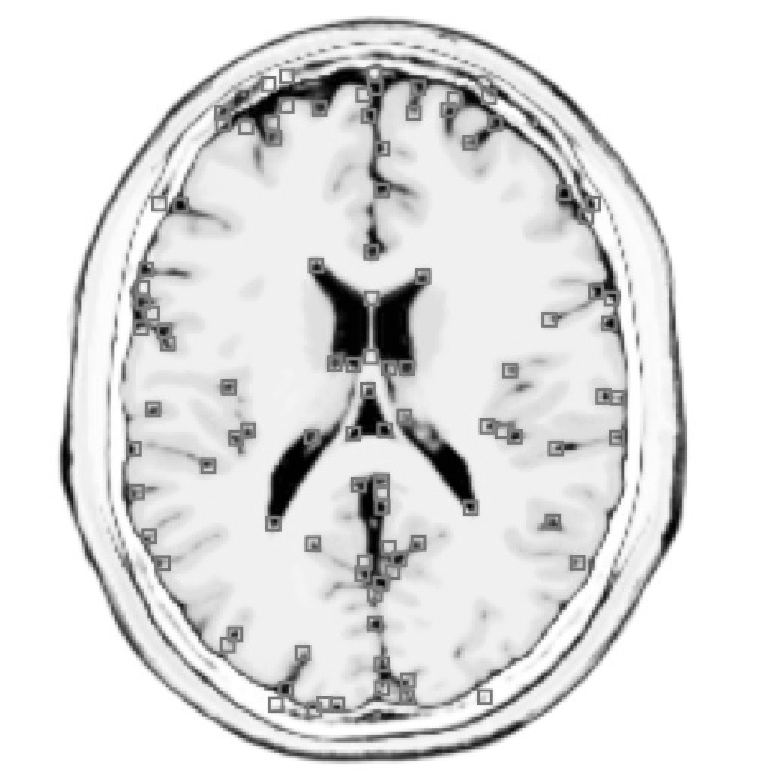

This paper proposes a hashing method that is, by construction, invariant under rotation of any angle and under scaling up to interpolation that preserves the significant structures. The presented hash function is built in two steps. First, given a simple salient point detector (Sec. 2.1), a smoothed version of the Harris corner detector [4], a saliency graph is constructed (Sec. 2.2). This structure is a (weighted) undirected graph connecting geographically close salient points. Second, the graph Fourier transform of a function defined on the graph, that is, its spectrum in the Laplacian graph eigenvector basis, is computed (Sec. 3). The use of this graph Fourier transform makes the hash independent of the salient point selection order. Moreover, in order to ensure invariance under transformations of the image, both the feature points selection and the definition of the function need to be invariant. A particular attention is therefore brought to the invariance of these last two elements. Sec. 4 presents finally the results of the method applied on the Brainweb database of brain MRI images [6] and on the ORL Database of Faces [11].

for some (typically set to ). Corners are then defined as the local maxima of the cornerness (as illustrated on Fig. 1), that is,

The databases used in our experiments are a T2-modulation volume MRI cut into slices along the directions, from the Brainweb simulator [6] and the ORL Database of faces [11]. In order to test the ISH, three sets of transformations have been applied on these images: (i) 9 rotations of angles between and , (ii) scalings of factors between and , (iii) and 9 random combinations of these rotations and scalings. A schematic illustration of the face image manifold (that has a polar representation for each image) is shown in Fig. 1.

For each image, the number of extracted salient points was set555When the number of salient points was smaller than , the distances , , and have been computed relatively to the smallest hash size. to maximum, the Gaussian kernel used for saliency detection has a standard deviation of 2.5% of the graph diameter . For the value of the connectivity radius (Sec. 2.2), good results have been obtained if . With this value, each node in the resulting saliency graphs were connected to an average of 5 other nodes.

The ROC curves testing rotation invariance, scaling invariance, and mixed rotation and scaling invariance have been computed for the two databases and for , and . For these two last distances, the ROC curves have been obtained by keeping only the first eigenvalues and GFT coefficients. The ROC curves testing mixed rotation and scaling are shown in Fig. 2 for the two databases. All the related AUCs are summarized in Fig. 3.

For the brain MRI database, achieves sensitivities over 90% with false positives rates lower than 10%. Under rotation only, a sensitivity of 95% with a false positives rate of 8% is achieved. Results for the ORL Database of Faces were slightly worse due to the lower number of salient points detected. For all faces, the maximum possible number of salient points, i.e., all the local maxima of the cornerness function, was systematically lower than the imposed maximum of . The hashing was therefore more sensitive to the variations of salient point positions between different transformation of the same image.